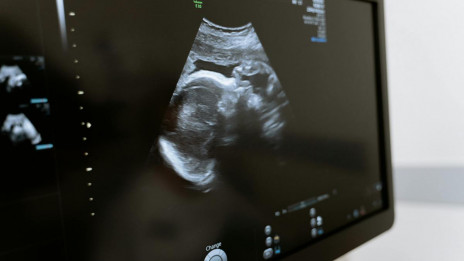

Evropski poslanci bodo danes glasovali o državljanski pobudi My voice, my choice – Moj glas, moja izbira. Komisija škofovskih konferenc Evropske unije (COMECE) ob tem opozarja, da je urejanje ...